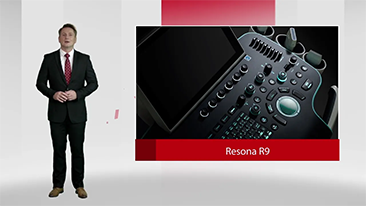

As solu??es de imagem geral Mindray Resona ajudam mĂŠdicos a obter resultados mais precisos e eficientes de diagnĂłstico e tratamento por meio de sondas de aplica??o de subdivis?es abrangentes e ferramentas eficientes de aplica??o clĂnica.

Produtos para imagem geral